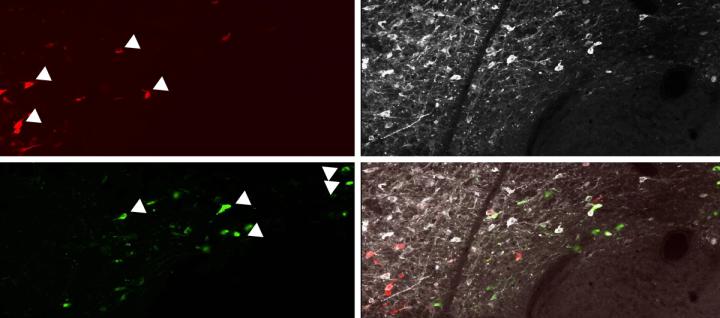

Freedom from fear: dopamine’s role in unlearning fearful associations

Credit: RIKEN National Science Institute Researchers at the RIKEN Center for Brain Science have discovered a circuit in the brain...